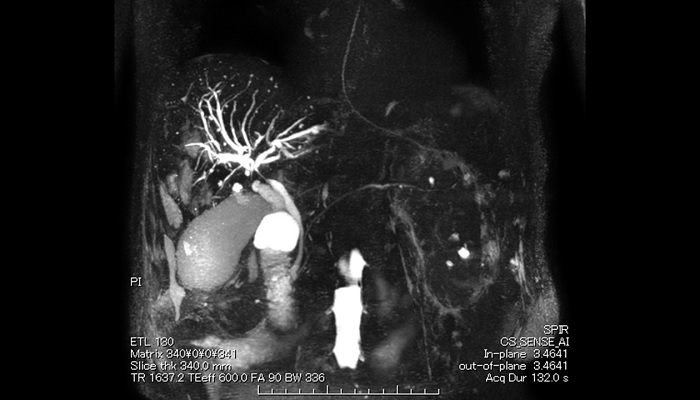

次に、日本発の非造影 MRA シーケンスである AV-TRANCE をご紹介されました。従来の非造影シーケンスでは、部分的な血管の信号低下がみられることがあり、狭窄を否定できないことがあります。AV-TRANCE は、心電図同期や呼吸同期が不要ながら、アーチファクトや脈管の信号ムラが極めて少ないため、安心して狭窄・閉塞を診断できると述べられました。また、術後遠隔期の大血管評価や先天性心疾患において、複雑な解剖学的形態を非侵襲的・簡便に把握できると、AV-TRANCE の有用性を強調されました。